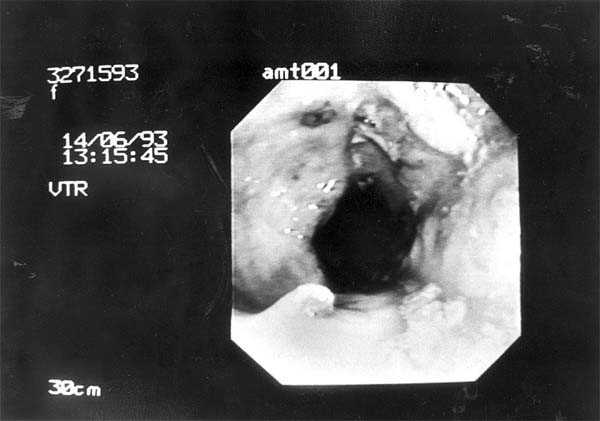

| Voorkomen is beter dan genezen. In Engeland start deze maand een proefproject voor onderzoek naar dikkedarmkanker. Zijn er aanwijzingen dat er iets mis is, dan kan via inwendig onderzoek van de dikke darm meer duidelijkheid worden verkregen. Archieffoto RD |